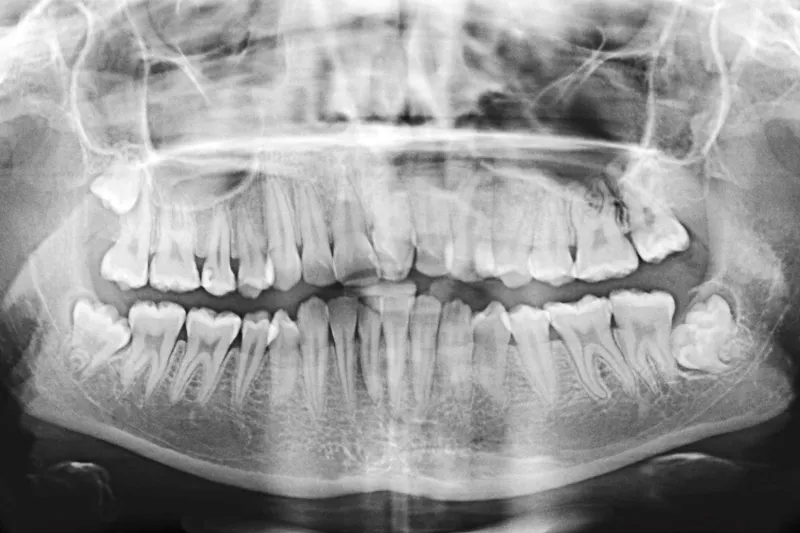

A744 figur 3

Patienttilfælde – En 12-årig pige udviklede i forbindelse med behandling i generel anæstesi malign hypertermi. Tilstanden blev identificeret hurtigt, og adækvat behandling blev iværksat involverende bl.a. afkøling med håndklæder vædet i sprit og koldt vand samt intravenøs behandling med Dantrolen. Patienten blev stabiliseret og overført i intuberet tilstand til Aarhus Universitetshospital med henblik på videre behandling. Hun blev udskrevet efter 16 dage. Efterfølgende havde hun gener i form af træthed og hovedpine ved langvarig fysisk aktivitet. Disse symptomer er i dag aftaget betydeligt. Hun er således i dag meget lidt generet heraf og har en helt normal hverdag.